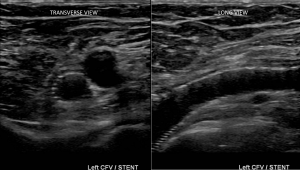

Obviously, the most common first study most patients will receive is duplex ultrasonography. But this modality cannot show the compressed vein in the pelvis. Abnormal waveforms with diminished respiratory variation in the common femoral vein can suggest more proximal obstruction, though. These too, however, may be absent with partially occlusive clots.

Above, is an image showing an example of May Thurner Syndrome as seen by CT angiography. Below, please note that the compression may lead to more extensive clot than just up to the compression, perhaps due to sluggish blood flow: